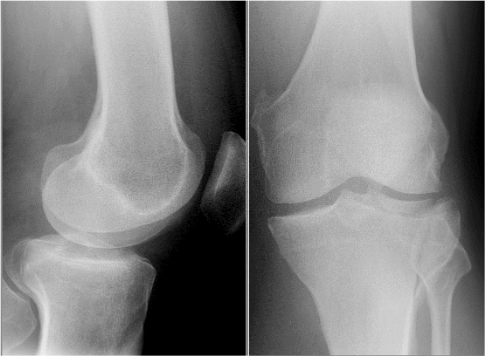

What is this ?

What causes it ?

Patella dislocation

Cause:

The alignment of the femoral and tibial shafts is such that the quadriceps pulls the patella superiorly and laterally

Increase risk with females

Knee effusion increases the risk of patella dislocation because vastus medialis quickly wastes.